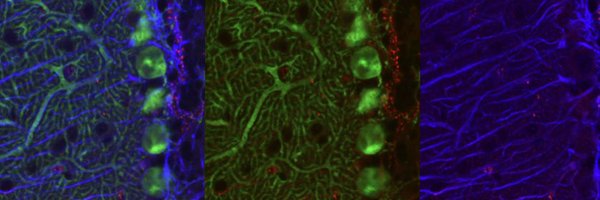

New publication!🚨 Using a life course approach in 5XFAD mice, we detected early increases in TSPO. In mice and familial AD cases, TSPO rises with amyloid buildup—especially in microglia near plaques. #Alzheimers #Neuroinflammation #TSPO @fiustempel @fiu https://t.co/PMrOhzMe46